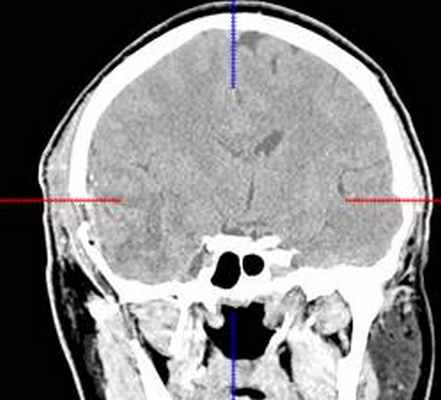

КТ головного мозга с контрастным усилением (24.03.2015): объемное кистозно-солидное образование правой теменно-височно-лобной области. Дислокационный синдром.

22.10.2015 была выполнена операция: микрохирургическое удаление опухоли правой височной доли под интраоперационными навигационным контролем и с интраоперационной фотодинамической терапией.

КТ головного мозга (23.10.2015): не выявило признаков кровоизлияния или каких-либо других хирургических осложнений в области оперативного вмешательства.